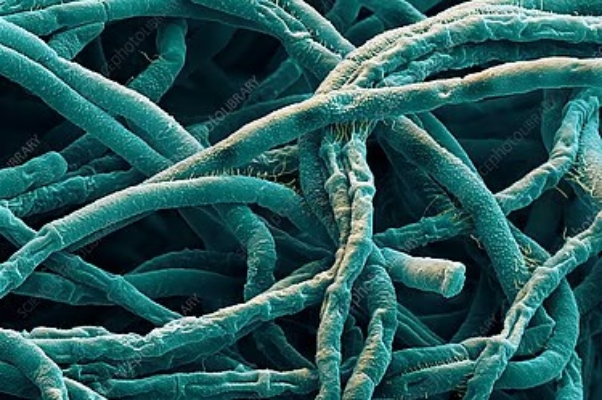

প্রতীকী ছবি: প্রথম আলো